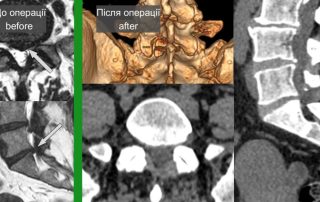

Складний випадок нагноєння хребта

У переважній більшості випадків нагноєння хребта зустрічається на поперековому, рідше на грудному рівні. У нашого пацієнта виникло нагноєння (спондиліт з епідуральним абсцесом) на верхньошийному рівні – на рівні 1-2 шийних [...]